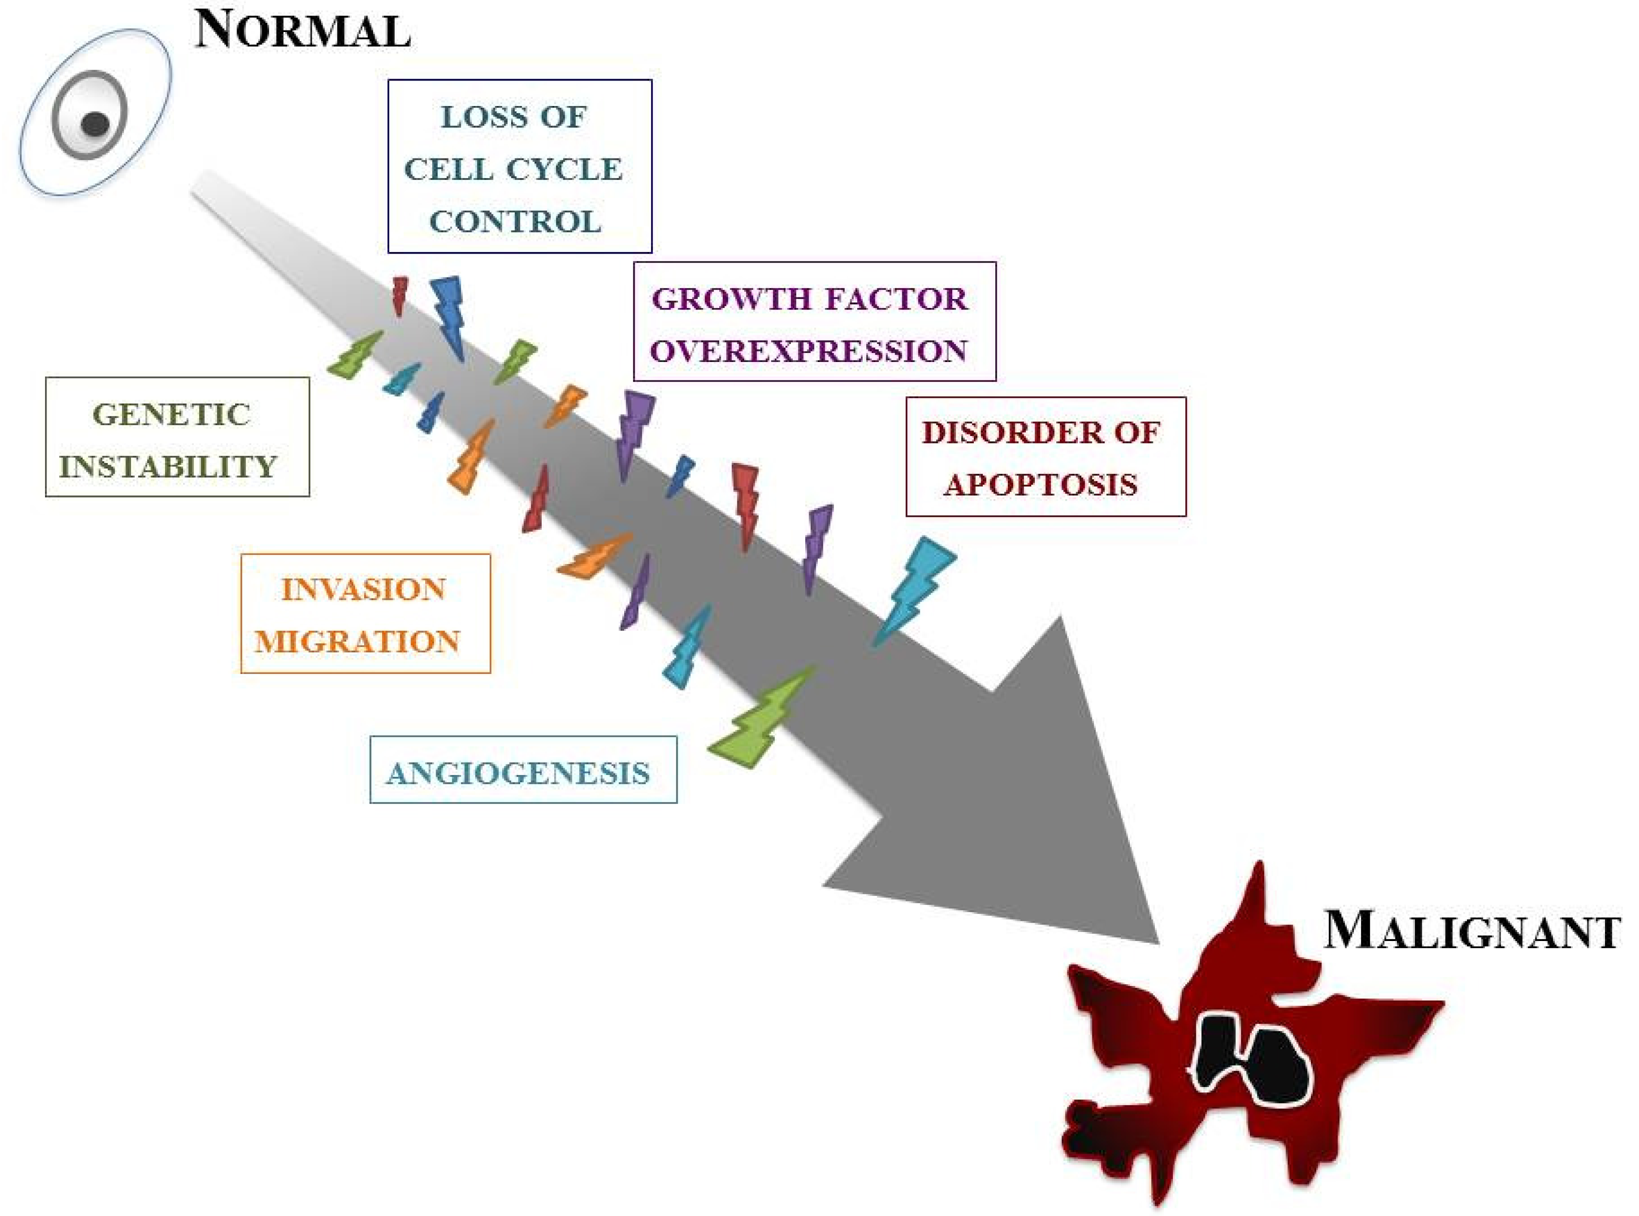

Our knowledge of the molecular biology of GBM has increased markedly over the last two decades. GBM cells are subjected to many kinds of cellular dysfunction, which make themselves resistant to various anti-GBM therapies. Six typical intracellular events that characterize glioma are overviewed below, but it should be stressed that such events do not arise in isolation; a combination of multiple tumorigenic events cause and sustain GBM (Figure 2).

The first event is loss of cell cycle control. The progression of the normal cell cycle is under strict control. However, glioma cells develop means for evading such control, giving them a growth benefit. The cell cycle checkpoint that has received the most attention is the G1–S phase transition. p16INK4a/cyclin-dependent kinase (CDK)-4/RB (retinoblastoma) 1 pathway, one of the major pathways controlling this checkpoint, involves p16, CDK-4, cyclin D1, and RB1 [9]. The CDK/cyclin D1 complex phosphorylates RB1, thereby inducing release of the E2F transcription factor that activates genes involved in the G1/S transition [10]. Many of the genetic defects in growth regulatory molecules occur preferentially in malignant, rather than low-grade, gliomas. Alterations of at least one component of this pathway occur in many anaplastic astrocytomas and in the vast majority of GBMs [11,12]. Nearly all high-grade tumors have impairments of this single critical cell cycle control pathway. It is likely as well that less profound defects in cell cycle regulation occur in low-grade gliomas; for instance, p53 gene mutations may affect both the G1–S and G2–M checkpoints.

The second event is overexpression of growth factors and their receptors. A variety of growth factors such as epidermal growth factor receptor (EGFR), platelet-derived growth factor (PDGF), basic fibroblast growth factor (bFGF, FGF-2), transforming growth factor (TGF)-α, and insulin-like growth factor (IGF)-1 are overexpressed in GBM and thus provide a growth advantage to neoplastic cells. Generally, glioma cells express both the growth factor ligands and their receptors, setting up an autocrine growth-promoting loop. Of these, EGFR and PDGF have been best characterized in GBMs [13,14]. EGFR is a transmembrane receptor responsible for sensing extracellular ligands, such as EGF and TGF-α, and for transducing this proliferation signal.

Angiogenesis is also an important feature. A dramatic sequence of angiogenic alterations occurs in the progression to GBMs, which in MRI appears as ring-like contrast enhancements that surround rapidly growing tumors [15]. Malignant gliomas are vascular tumors, and the histological presence of microvascular proliferation indicates a high grade. Angiogenic molecules have been found in malignant gliomas, primarily in GBMs [16]. Vascular endothelial growth factor (VEGF) is the most clearly implicated and an endothelial cell mitogenic factor that is expressed most often adjacent to areas of necrosis but not in low-grade astrocytomas. This suggests that the malignant progression from low-grade astrocytomas to GBMs includes an “angiogenic switch”.

One of the key features of GBMs, invasion and migration, is their diffuse infiltration of the surrounding neural net. The expression of several extracellular matrix (ECM) molecules and cell surface receptors may modulate signal transduction and influence invasion and migration in GBMs [5,17,18]. These include cytoskeletal proteins; signaling molecules that mediate interactions between the microenvironment and the cytoskeleton; cell surface receptors involved in cell migration such as transmembrane adhesion molecules; and components of ECM, including proteases.

Abnormality of apoptosis should be mentioned. Apoptosis refers to cell death that occurs in a programmed manner, characterized by non-inflammatory cellular condensation. Glioma cells may develop means not only for increasing proliferation but for abrogating apoptosis as well. A number of genes involved in gliomagenesis have roles in apoptosis, most notably p53 [19,20]. p53 mutations disturb the normal glial apoptotic response that would follow growth factor overexpression in low-grade gliomas, allowing further progression [21].

The last intracellular event is genetic instability. An essential feature of low-grade gliomas is their nearly universal progression to higher-grade lesions over time. Such malignant progression is related to the emergence of more malignant clones. Genomic instability, a feature of many tumors, encourages further genomic damage, thus allowing the eventual selection of more malignant clones [22]. Mutations in p53, also known as “guardian of the genome”, may therefore lead to tumor progression through genomic instability. Patients with syndromes of genomic instability, such as the Turcot syndrome, have an increased susceptibility to malignant gliomas [23].